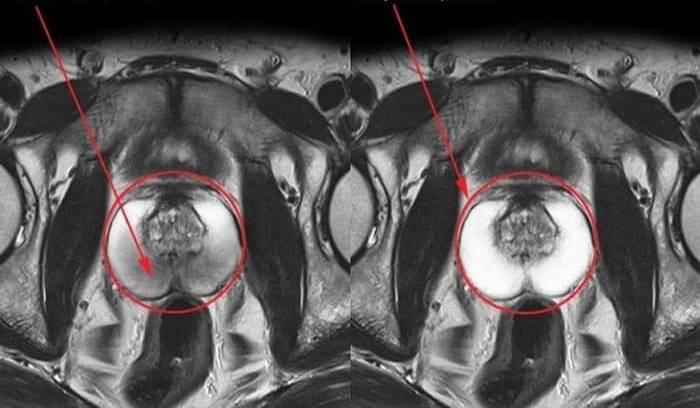

- Prostatitdən tam sağalma (bir necə ay ərzində). 89% (infeksion iltihab zamanı) və 94% (qeyri-infeksion iltihab zamanı) xəstələrdə. Digərlərində əhəmiyyətli dərəcədə yaxşılaşma müşahidə olundu. Bu, ən obyektiv muayinə üsulu - prostatın MRT-si ilə qeydə alınıb.